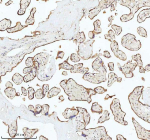

Immunohistochemical staining of MALSU1 using anti-MALSU1 antibody. MALSU1 was detected in a paraffin-embedded section of human placenta tissue. Heat mediated antigen retrieval was performed in EDTA buffer (pH 8.0, epitope retrieval solution). The tissue section was blocked with 10% goat serum. The tissue section was then incubated with 2 ug/ml rabbit anti-MALSU1 antibody overnight at 4oC. Peroxidase Conjugated Goat Anti-rabbit IgG was used as secondary antibody and incubated for 30 minutes at 37oC. The tissue section was developed using an HRP secondary and DAB substrate.